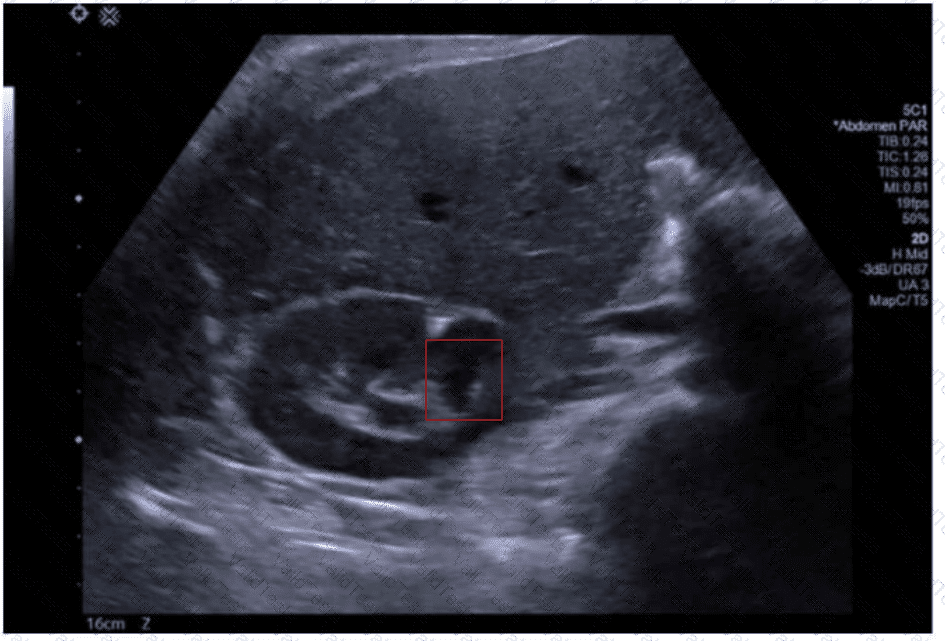

An ultrasound of a fetus

The ultrasound image shows a transverse (axial) view of the fetal abdomen. Notably, there is abnormal continuity of renal parenchyma across the midline anterior to the aorta, forming a U- or horseshoe-shaped structure. This is characteristic of a congenital anomaly known as a horseshoe kidney.

Horseshoe kidney is the most common fusion anomaly of the kidneys, occurring in approximately 1 in 400–600 live births. It results from fusion of the lower poles of both kidneys during fetal development. On prenatal ultrasound, this anomaly can be suspected when the kidneys appear closer to the midline than usual and are connected by an isthmus of renal tissue or fibrous band that crosses anterior to the spine and great vessels.

Typical sonographic findings include:

Abnormally located kidneys, often lower than expected

Renal fusion across the midline (usually at the lower poles)

Possible associated hydronephrosis or malrotation